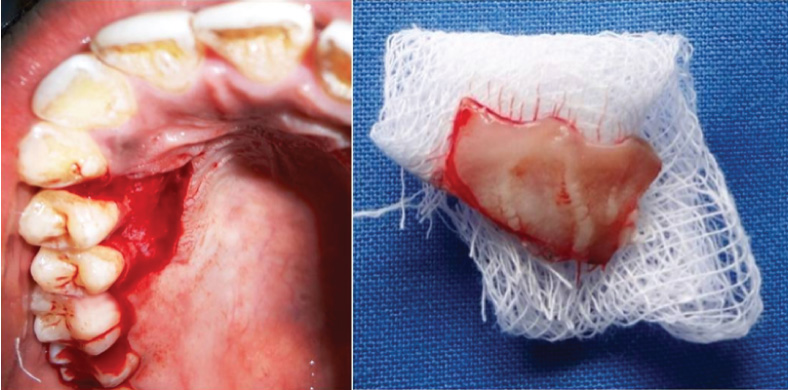

Following a greater palatine nerve block, the donor gingival unit graft was harvested from the palatal aspect of maxillary first and second premolar using a 15 size BP blade. The graft was harvested by including the gingival margin along with the interdental papilla with a thickness of about 1 to 1.5 mm. The graft was separated along the outline using a small tissue holding pliers and the overhanging tissues were trimmed from the undersurface of the graft [Table/Fig-4].

The gingival unit transfer graft harvested from the palatal region of 14 and 15. (Images from left to right)